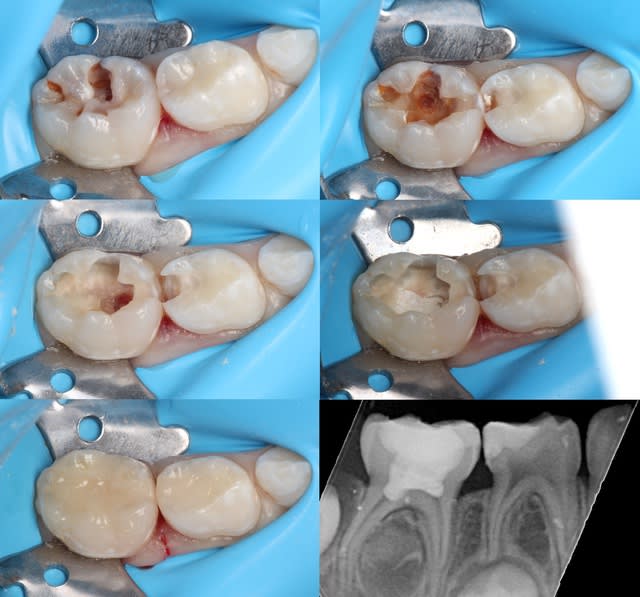

Peu de temps après, il fait une exposition pulpaire sur une 26 présentant une carie pourtant à peine dentinaire. L'exposition baigne dans la salive, la digue n'est pas posée, contrairement aux consignes du service. "Gentil", j'explique que l'exposition était évitable et constitue un mauvais facteur pour le pronostic de la dent, d'autant plus au vu de la contamination salivaire. Faciès bovin, aucune réaction. J'explique en d'autres termes : "Tu vois cette petite fille de 7 ans ? Tu comprends que sa 26 est probablement perdue au long terme par ton acte ?". Aucune réaction. J'insiste et lui demande sincèrement : "Ça ne te fait rien ? Tu ne te sens pas un peu triste ?". Il répond nonchalamment : "J'sais pas, faut qu'j'aille chercher une digue, c'est ça ?".

Au bout d'une année de ce comportement, j'émets un avis lors des délibérations. Il s’avère alors que cet avis est le même dans d'autres disciplines. Les quotas/notes sont à la limite de la moyenne. Après discussion, une décision collégiale est prise : les quotas/notes ne sont pas "remontés" et l'étudiant redouble.

Il vient se plaindre : "Vous m'avez fait redoubler pour une pulpo !". Je ne doute pas qu'il dira à ses amis "J'ai redoublé parce que TiGabi il m'aimait pas !". Et dans 10 ans, il écrira sur Eugenol : "Les profs à la fac, c'est rien que des salauds !".

De deux, tu penses que ton iconographie m'impressionne? Il n'y a rien de très compliqué.

Je suis vraiment content que tu me dises ça. Cette iconographie me demande énormément de temps sur des enfants de 4-6 ans et dans le flux d'un cabinet libéral. Comme ce n'est "pas compliqué" et que tu as plein de conseils pour les enseignants, tu va pouvoir m'aider à préparer les cours ?